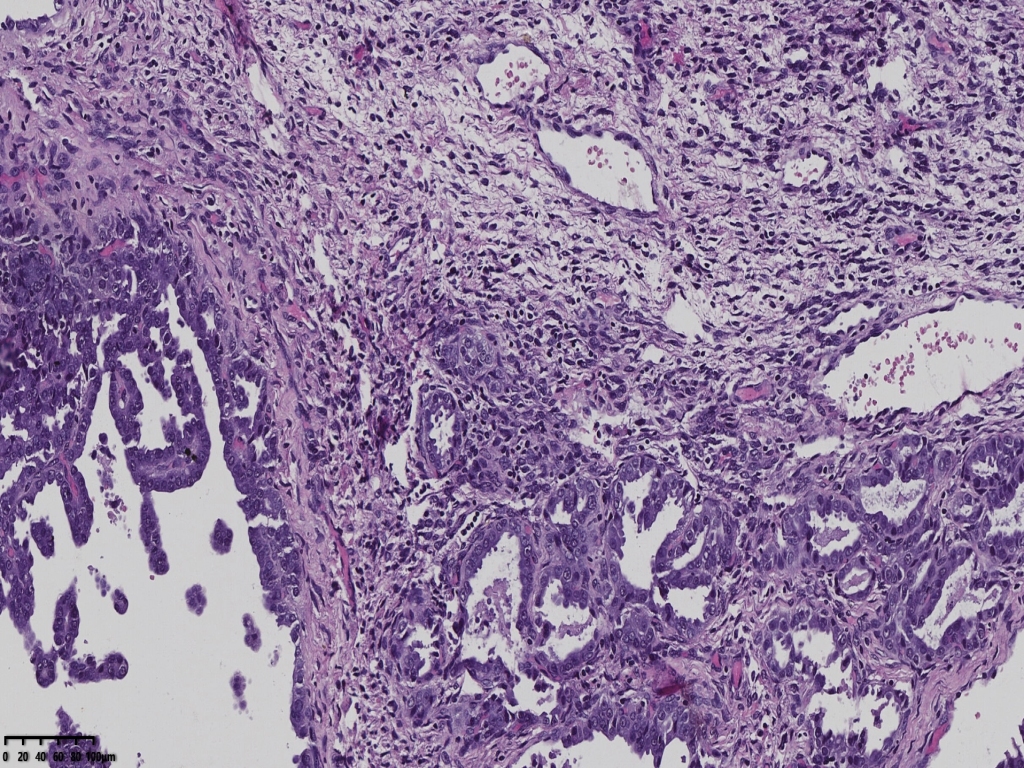

镜下可见肿物,腺样机构,密集,细胞异型

局部分区域腺体偏实性,细胞核大,周围胞浆空亮,会诊为子宫透明细胞癌,是不是就依据这一点?

宫颈管及宫颈管可见癌组织侵犯浅层,以腺样结构为主